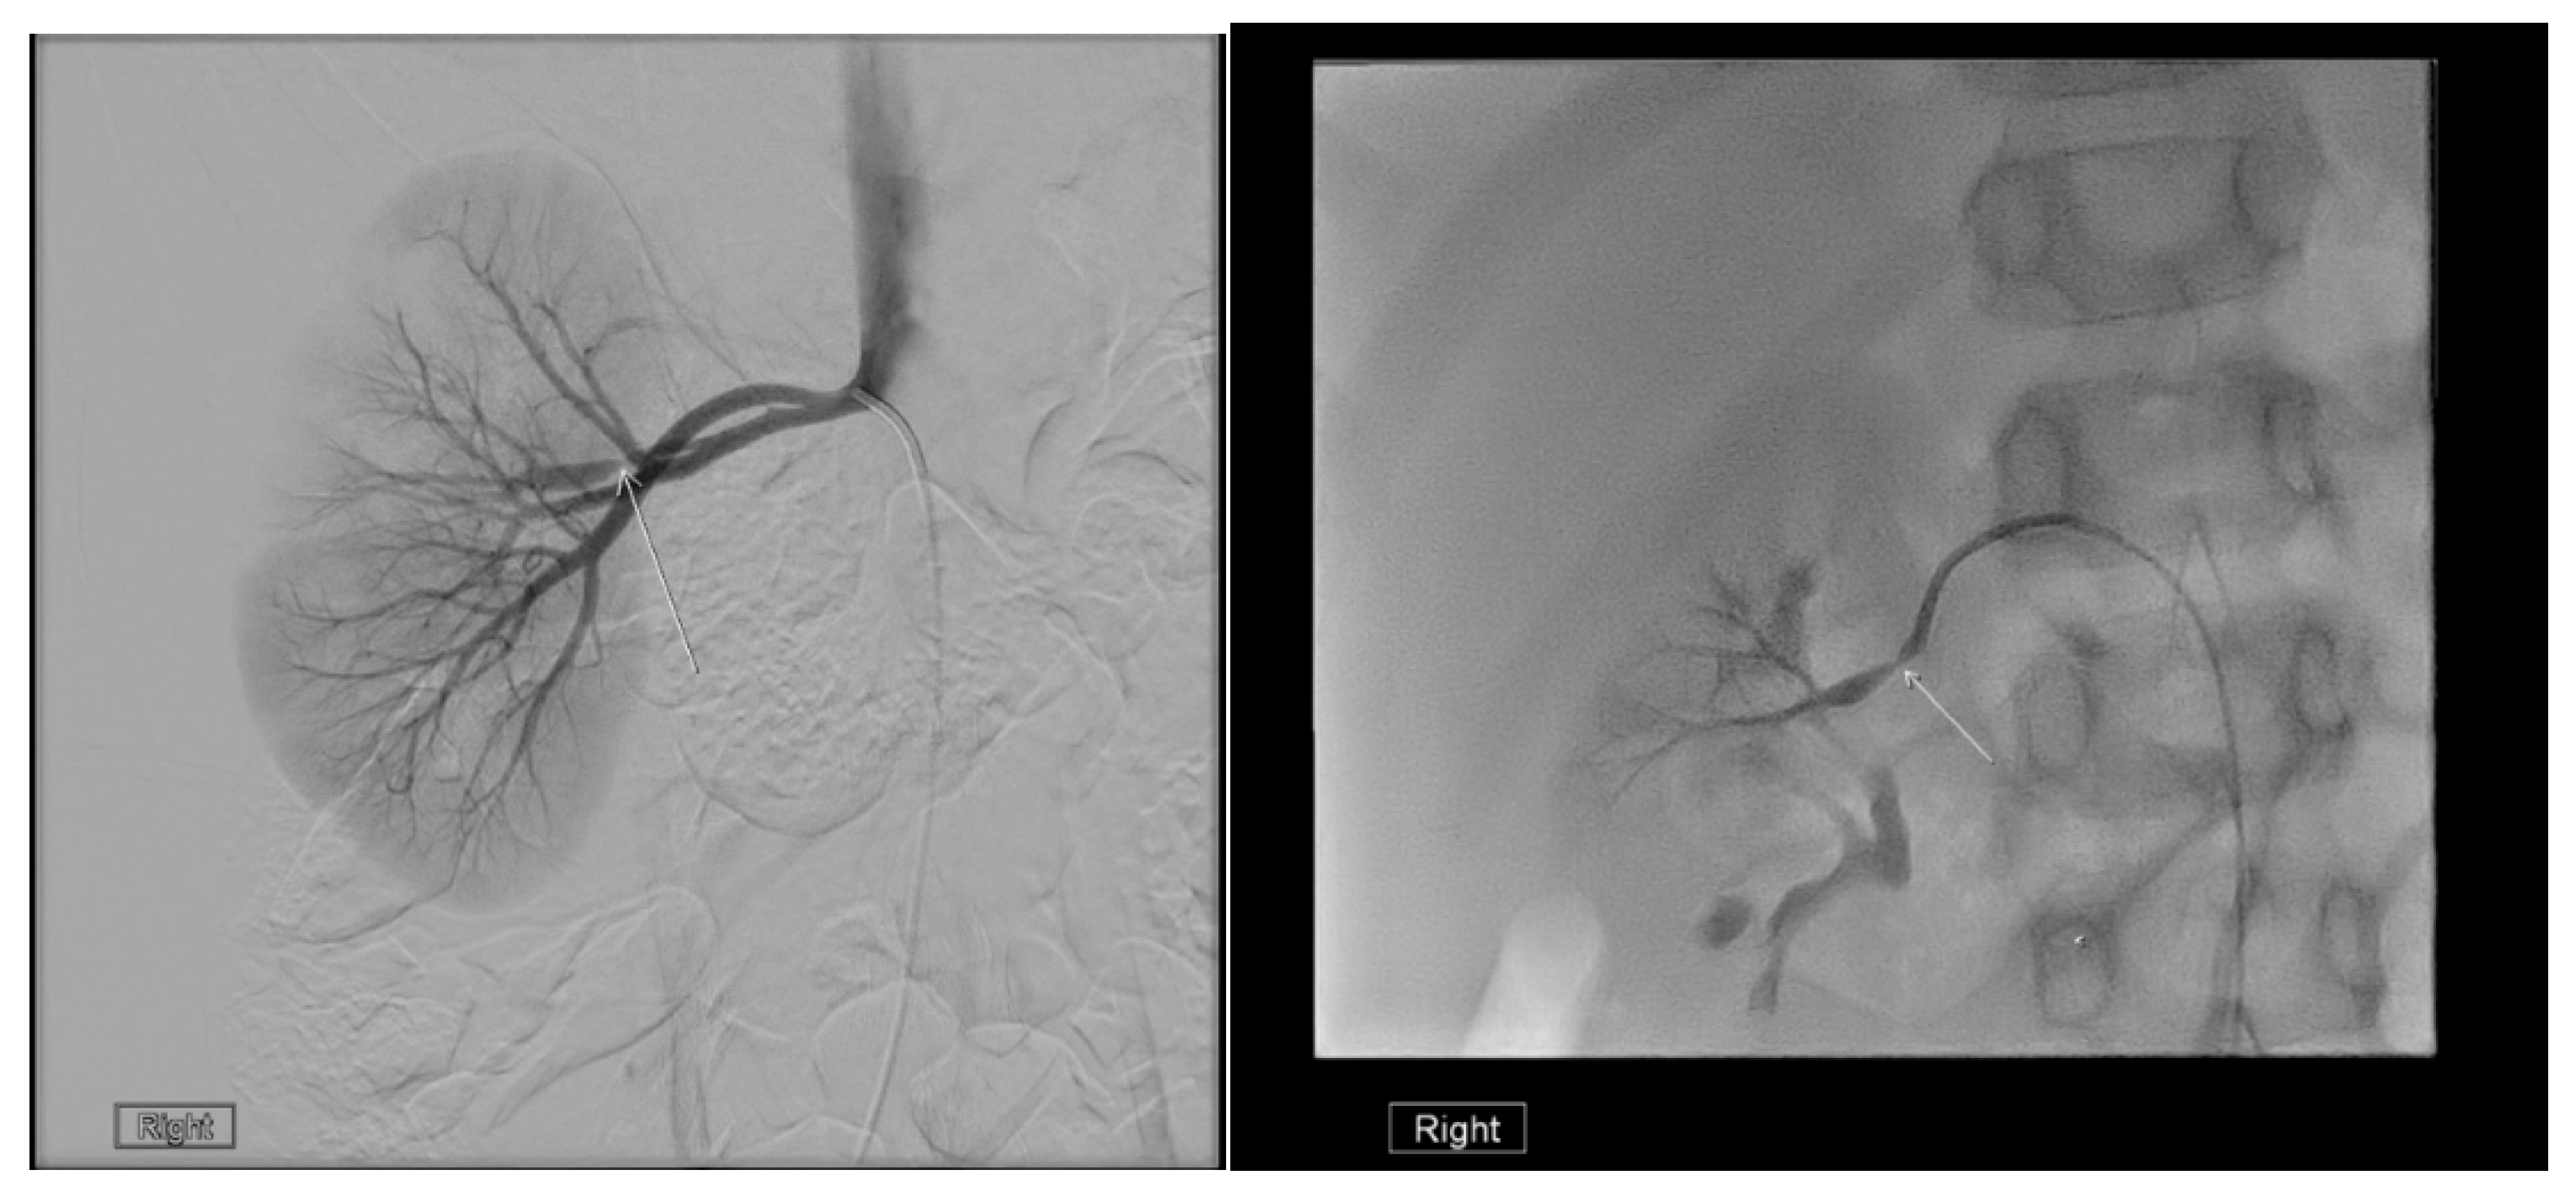

23. Urinary Tract Tumors

US is useful for initial tumor evaluation, but CT or MRI is needed to assess extent and metastases. It is particularly sensitive for detecting bladder tumors in children [85]. Both US and CT aid in evaluating and monitoring Wilms tumor [86,87].

For Wilms tumor staging, US should assess the abdomen and pelvis, while X-rays and CT are used for the chest, abdomen, and pelvis. MRI provides a comprehensive abdominal view and is effective for evaluation (Figure 27) [86]. US screens for tumor recurrence, though CT and MRI may be required to detect nephrogenic rests, the precursors of Wilms tumor [86]. US is preferred for screening high-risk children, such as those with Beckwith–Wiedemann syndrome, hemihypertrophy, or Denys–Drash syndrome [88].

Figure 27. MRI shows bilateral nephroblastomatosis with bilateral nephroblastoma in a 2-year-old female.

Medicina 61 00696 g027